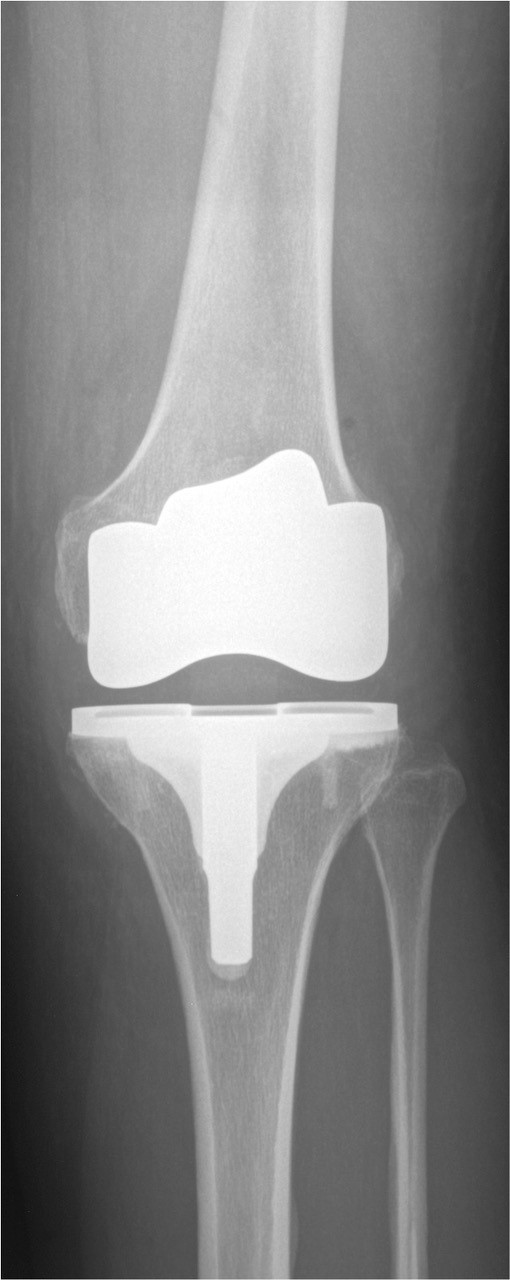

Das Kniegelenk besteht aus drei Gelenkkompartimenten: einem inneren, zentralen und äußeren Kompartiment. Die Kniescheibe bildet ein Widerlager und gleitet über den Oberschenkelknochen. Prinzipiell ist ein isolierter oder kombinierter Verschleiß vom inneren oder äußeren Gelenkkompartiment sowie auch dem Kniescheibenwiderlager möglich. Erkennt man die Erkrankung früh genug und ist der Leidensdruck entsprechend, so kann man die einzelnen Kompartimente isoliert ersetzen.

Wir halten ein großes Portfolio moderner und bewährter Prothesen vor, die sich entsprechend den o.g. Ausführungen vom Prothesendesign unterscheiden. Innerhalb des Designs liegen verschiedene Ausführungen und verschiedene Größen vor, so dass wir je nach Krankheitsbild für Sie eine individualisierte Versorgung anbieten können. Bei entsprechender Indikation kann der Kniegelenkersatz auch mit robotischer Unterstützung erfolgen, die Prinzipien werden in dem nachfolgenden Artikel aus FOCUS-Gesundheit 5/2023 verständlich dargestellt.

Sollte bei Ihnen eine Endoprothese in Frage kommen, wird durch Beurteilung verschiedener Faktoren der Prothesentyp aus dem o.g. Portfolio für Sie ausgesucht.

Während des Eingriffes wird Ihr Gelenk gegen ein künstliches Gelenk ausgetauscht. Der Eingriff dauert etwa ein bis eineinhalb Stunden und kann in Allgemein- oder Teilnarkose durchgeführt werden. Welche Art der Narkose für Sie in Frage kommt, wird Ihr Narkosearzt mit Ihnen besprechen. Durch das prä- und intraoperative Blutmanagement der Anästhesieabteilung werden Fremdblutkonserven normalerweise nicht benötigt. Am ersten postoperativen Tag werden Sie auf die Normalstation verlegt wo mit der Mobilisierung begonnen wird. Während des stationären Aufenthaltes werden Sie einen sicheren und selbständigen Gang wiedererlernen – in der Regel ohne Belastungseinschränkungen. Ein Hauptaugenmerk liegt in der Wiederherstellung der Beweglichkeit des Kniegelenkes. Bis zur Entlassung sollte ein Bewegungsausmaß von voller Streckung und mindestens 90° Beugung, unabhängig vom präoperativen Befund, vorliegen.